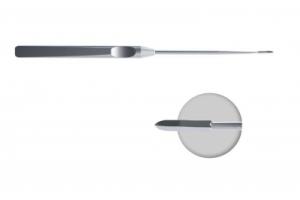

Троакар тупоконечный (обтюратор артроскопический хирургический тупой).

- ID: 0052234

- Артикул: AT-01400-1

Троакар пирамидальный (стилет артроскопический хирургический пирамидальный острый).